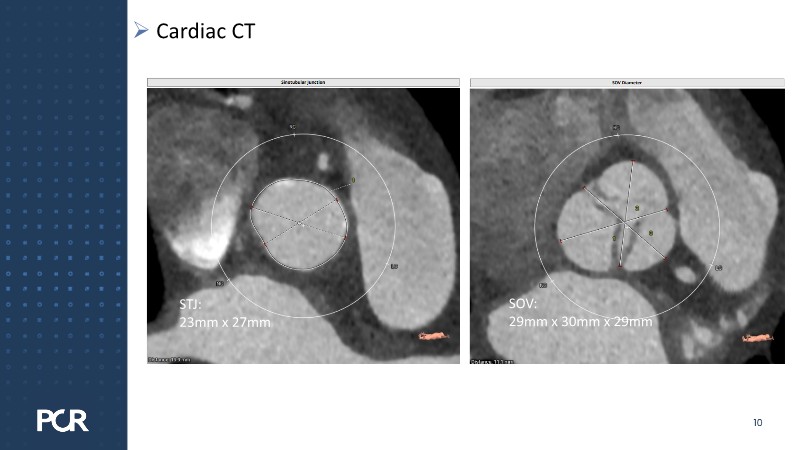

Discover how thoughtful index valve selection and implantation techniques can shape the long-term management of patients undergoing TAVI. This PCR London Valves 2025 session highlights treatment considerations for low- and intermediate-risk patients, explores how valve choice affects the feasibility of future interventions, and examines strategies to achieve optimal and durable clinical outcomes. Follow real patient case with imaging analysis, hemodynamic insights in small annuli, and discussions on planning for future revalving and coronary access.